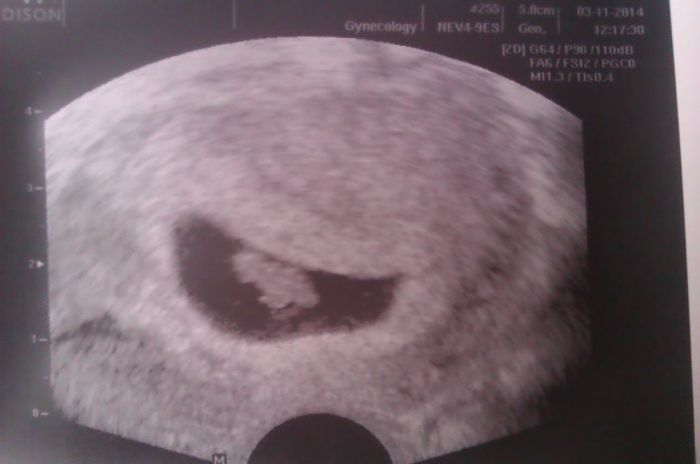

Ahoj holky tak píšu slíbené info.Dneska jsem byla u doktorky a podle MS bych měla být 8+3 a jsem 7+5 takže to za těch 14 dní drobek hezky dohnal, ještě mu chybí týden ale do snad dožene taky

slyšela sem už i srdíčko a na další kontrolu jdu za 14 dní.

Posílám i slíbenou fotečku a doufám že za chvíly tu budou i vaše